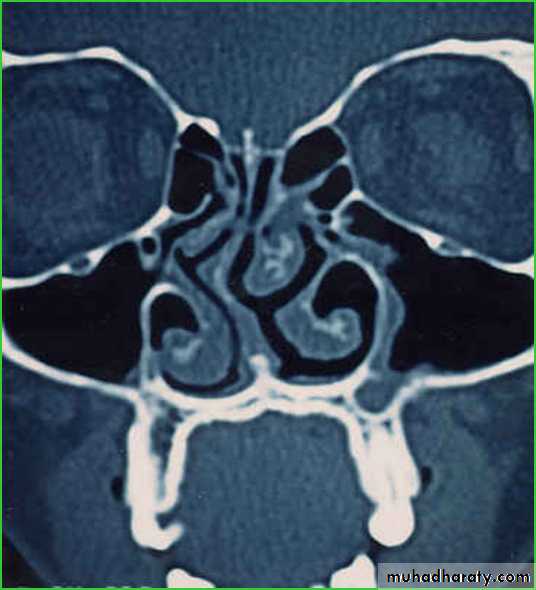

Are air-filled spaces in the facial & skull bonesThe paranasal sinuses consist of the paired frontal, ethmoid ,maxillary, and sphenoid sinuses.

Maxillary Sinus

The maxillary sinus usually is the largest of the paranasal sinuses and is situated in the body of the maxilla.Anterior wall:- The facial surface of maxilla.

Posterior wall:- The infratemporal surface.

Medial wall :- The nasal cavity.

The roof:- Floor of the orbit.

the floor is related to the roots of the premolars and molar

teeth.

The maxillary sinus drains into the middle meatus of the nasal cavity

Ethmoid Sinuses1he ethmoid sinuses consist of a variable number of separate cavities.

It lies between the upper part of the lateral nasal wall and the medial wall of the o:rbit.

Each sinus is divided into

1- anterior ethmoid sinus: - drains into middle meatus

2- posterior ethmoid :- drains into the superior meatus

Frontal Sinuses

The two frontal sinuses are contained within the frontal bone.

They are separated from each other by

a bony septum.

Each sinus is roughly triangular.

Extending upward above the medial end of the eyebrow and backward into the medial part of the roof of the orbit.

Each frontal sinus opens into the middle meatus via the nasofrontal recess.